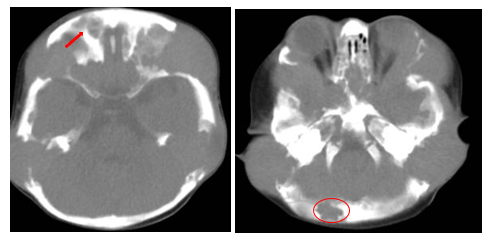

A subsequent CT scan of the brain, complete abdomen, and thorax showed soft tissue lesions that were homogeneous, well defined, and exhibited mild enhancement with contrast, eroding and altering the morphology of the skull cortex without infiltrating the brain parenchyma (Figure 2A & 2B). Additionally, multiple lytic lesions were identified in the sphenoid bone and vertebral bodies of C2, C3, and C5 vertebrae. Thoracic CT revealed lytic lesions in the vertebral bodies of T1, T3, T4, T6, and T7, along with pathological fractures of T5 and T9 (Figure 3A & 3B). Given the extensive bone involvement, the possibility of aggressive systemic disease was considered, including LCH, neuroblastoma, and metastatic rhabdoid tumors. Definitive histopathological examination of the previously biopsied tissue, complemented by immunohistochemistry, confirmed the diagnosis of Langerhans cell histiocytosis (LCH). Immunohistochemical staining was positive for S-100, CD68, PD-L1, and CD1a, which further confirmed the diagnosis. Due to the patient developing bilateral ear discharge, a mastoid CT scan was performed. The scan showed a loss of normal mastoid morphology with bony erosion caused by homogeneous soft tissue lesions bilaterally (right mastoid: 2.9 x 1.8 cm, left mastoid: 3.4 x 2.3 cm) (Figure 4A & 4B). These findings are consistent with the systemic spread of LCH, which affects the temporal bones.

Figure 2A&2B Cerebral CT scan of the patient- Evidence of soft tissue lesions, homogeneous, with well-defined borders, showing mild contrast enhancement in the occipital and frontal regions.